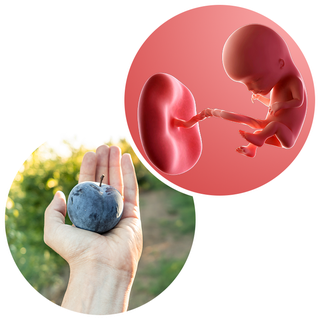

Your baby is now about the size of a plum, and hopefully you are starting to feel much better as the 1st trimester comes to a close.

Your baby, or foetus, is now 5.4cm long from head to bottom, which is about the size of a plum.